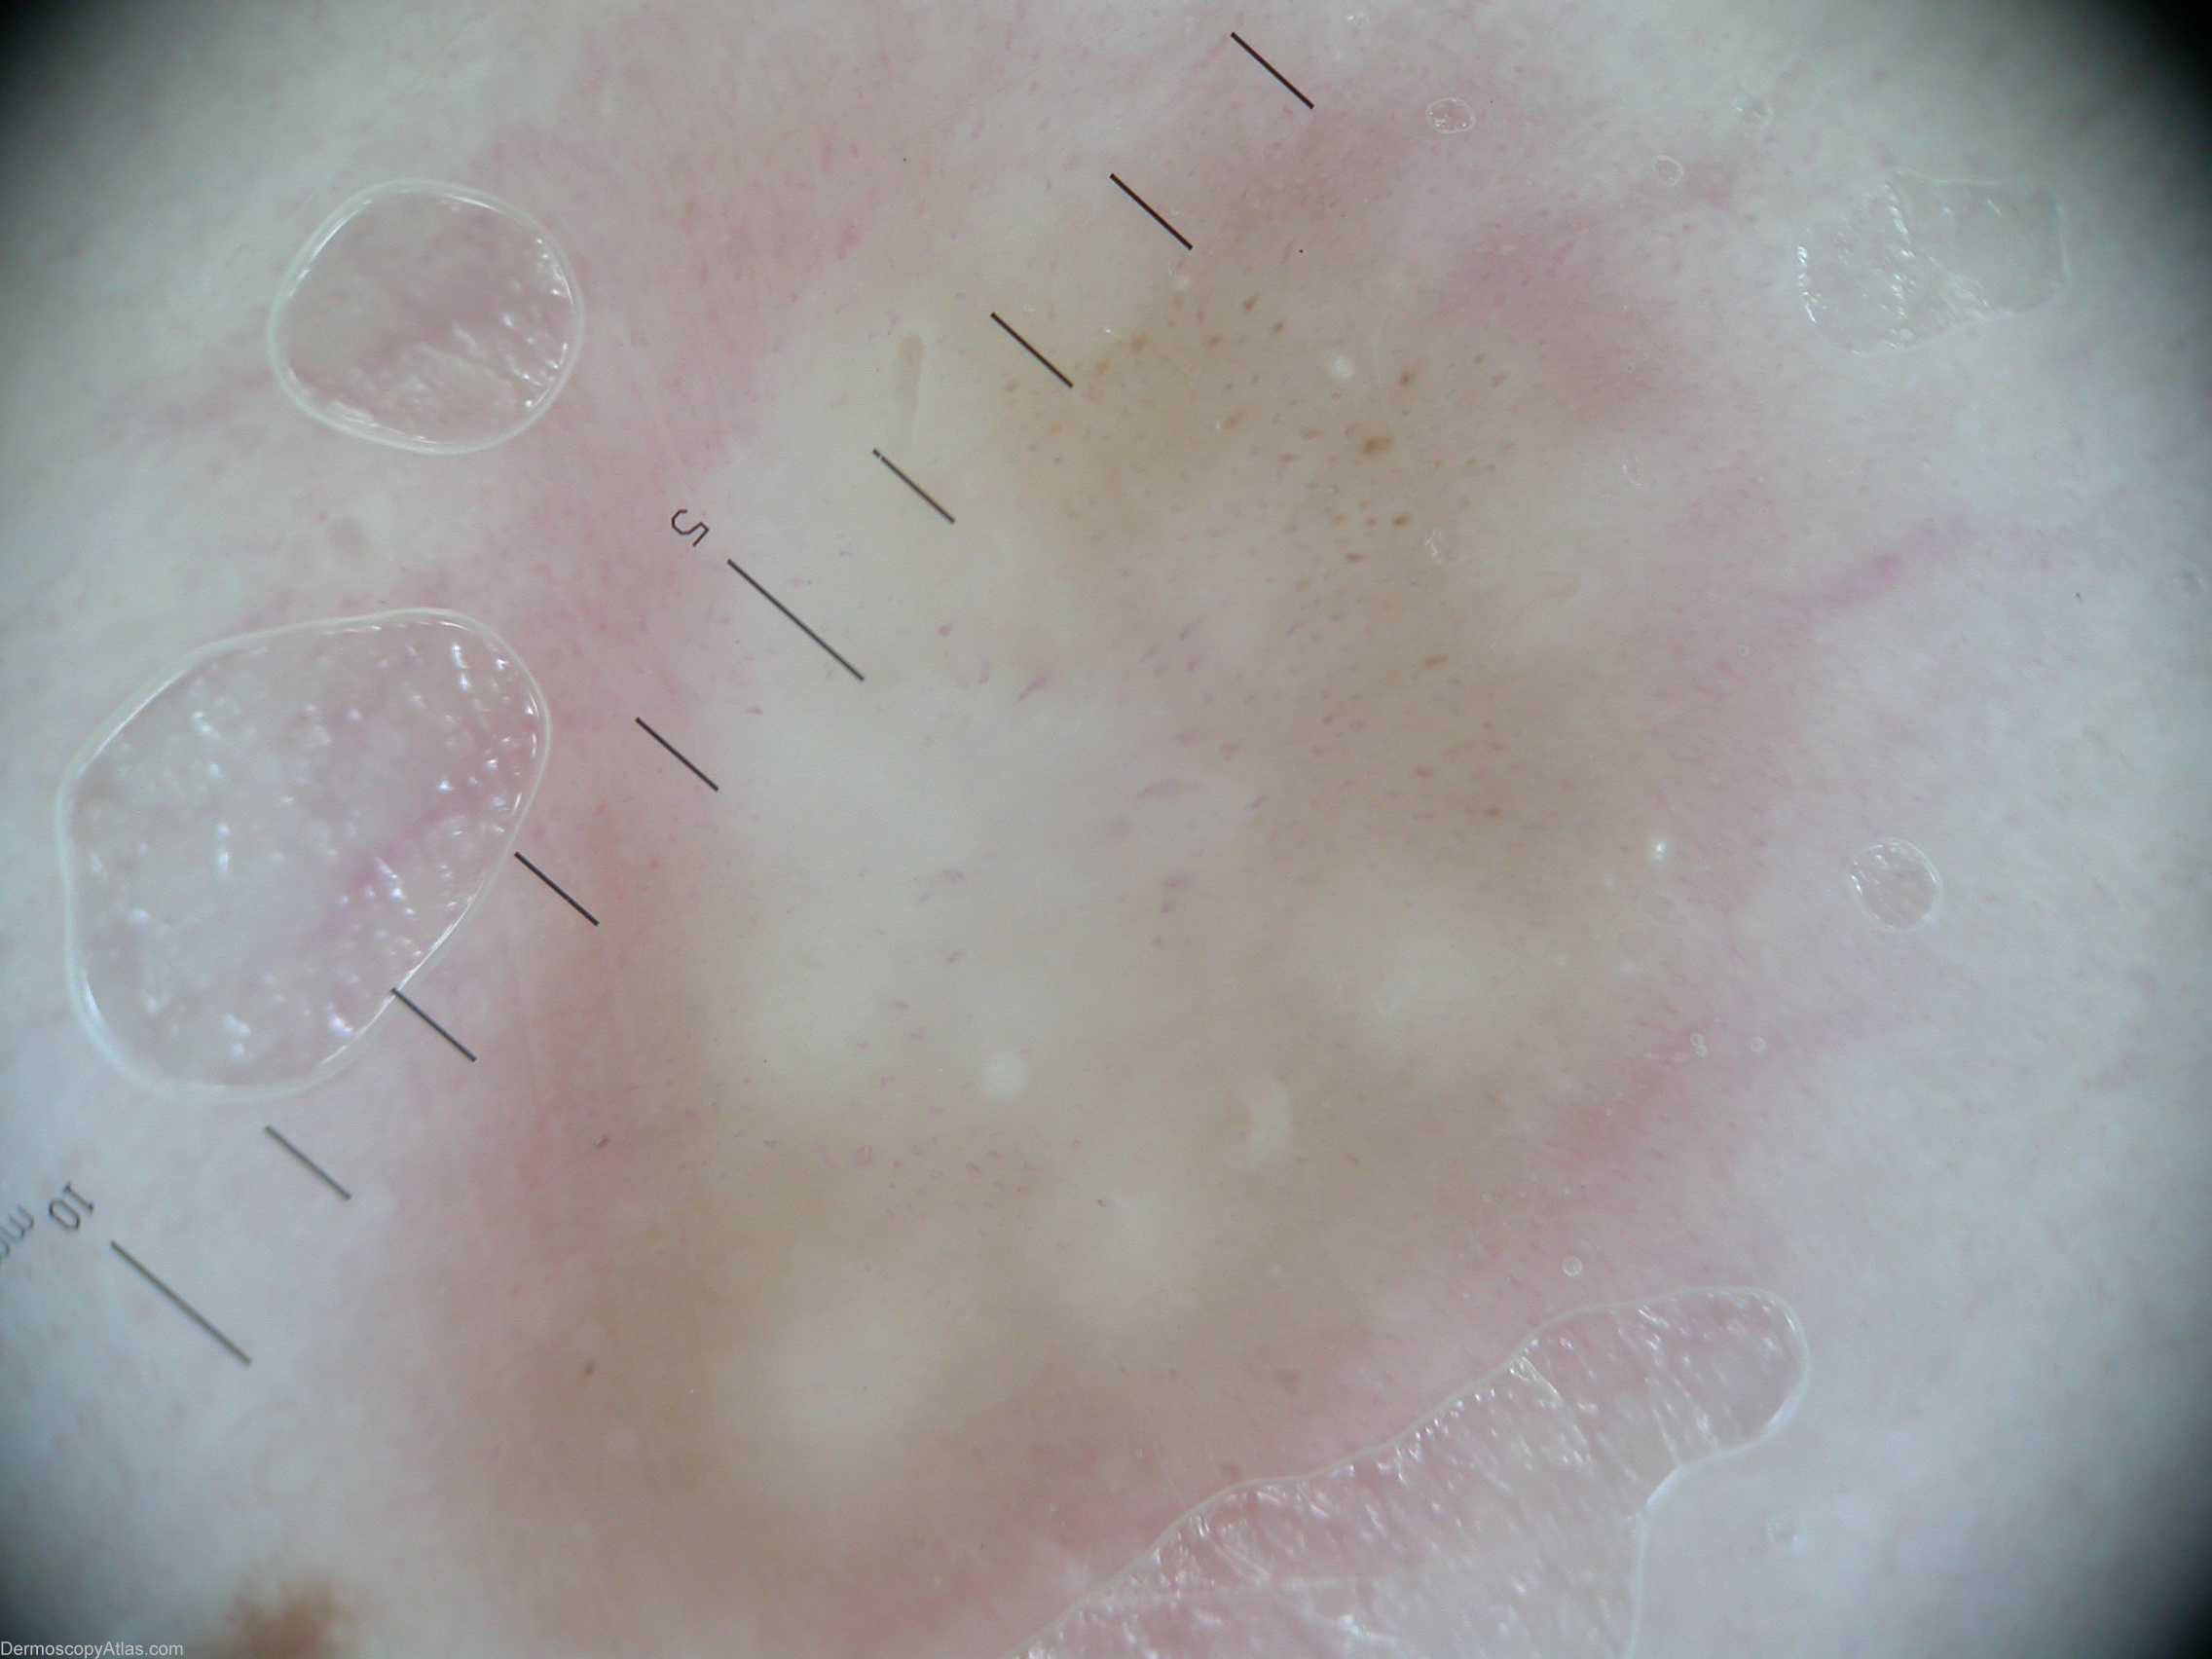

Diagnosis: Dermatofibroma